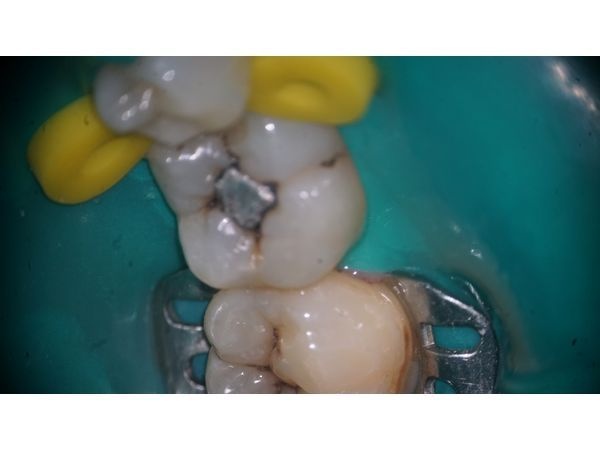

На жевательной поверхности 47 зуба установлена пломба из амальгамы. Краевое прилегание было нарушено. Под пломбой развивался кариес. С щёчной стороны определялся размягчённый пигментированный дентин. Моляр был наклонён в сторону отсутствующего зуба 46.

- сняли амальгамовую пломбу и обработали кариозные полости;

- установили постоянную пломбу из светоотверждаемого композита с учётом анатомии зуба;